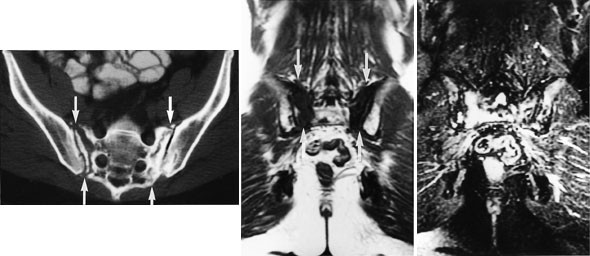

Strålebehandling svekker også beinsubstansen og disponerer for frakturer. Stråleinduserte insuffisiensfrakturer er hyppigst i bekkenet og hyppigst hos kvinner. MR viser tydelig ødemet som ledsager disse frakturene. Ødemet har lavt signal på T1-sekvensen og høyt signal på STIR-sekvensen (fig 4), altså signalforhold som likner på metastaser. Metastaser til strålebehandlet beinmarg er imidlertid meget sjeldent. Det er viktig at ødemet ikke feiltolkes som metastase, idet slik feiltolkning kan føre til tilleggsbestråling med ytterligere skade av beinet til følge. I en prospektiv serie av 18 kvinner som ble fulgt gjennom 30 måneder etter strålebehandling for cancer cervicis uteri ble det påvist ødemforandringer som uttrykk for frakturer hos 16. Ti av disse 16 pasientene hadde smerter (8).